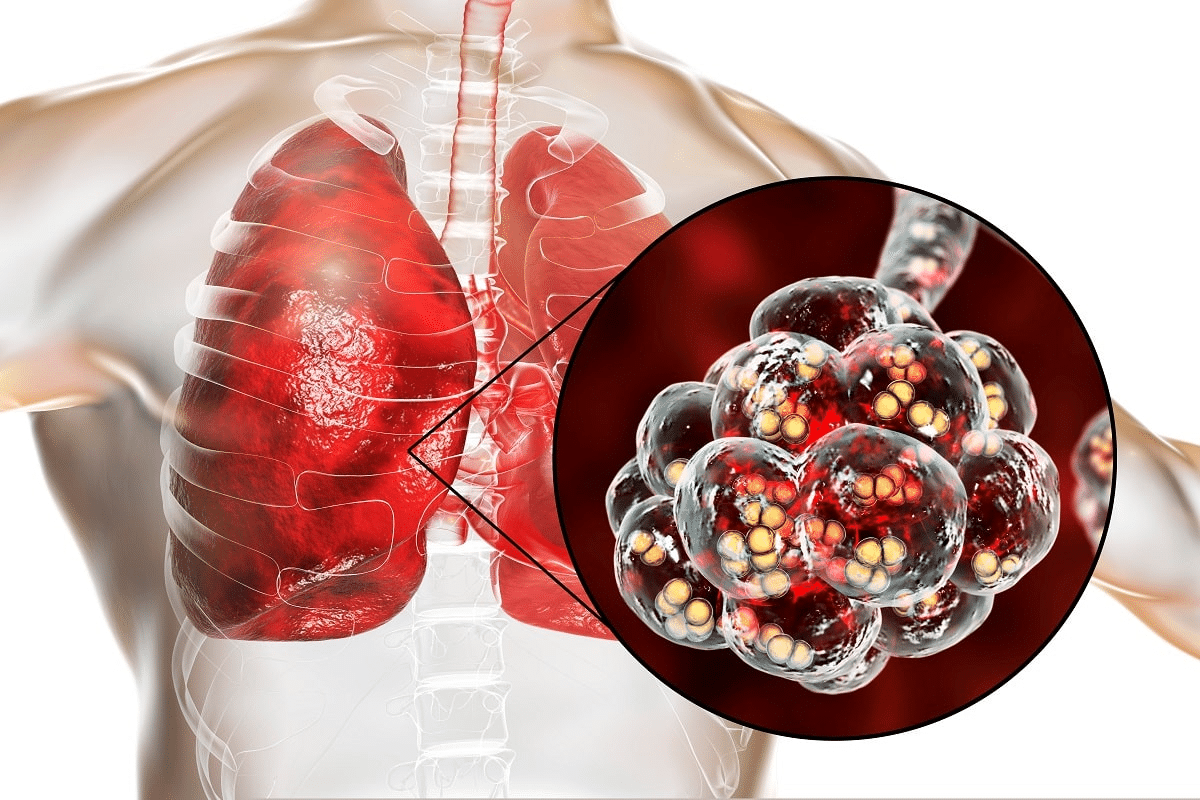

It’s important to know how a chest X-ray looks different when it shows pneumonia. At Liv Hospital, we focus on getting the right images to spot pneumonia early. This helps us treat it better.Detailed analysis showing the visual differences between pneumonia chest x ray vs normal lung fields clearly.

Pneumonia shows up as white spots on X-rays. These spots mean there’s inflammation and fluid in the lungs. On the other hand, healthy lungs look clear and sharp on X-rays. Our team uses the newest methods to spot pneumonia right away. This means we can give the right treatment fast.

Chest X-rays are key in finding lung problems and helping treat infections. They show the lungs clearly, helping doctors spot many respiratory issues, like pneumonia.

Chest X-rays are a non-invasive way to see the heart, lungs, and chest wall. They work by showing how different tissues absorb X-rays, creating images. This helps doctors see lung problems, like pneumonia.

Chest X-rays are vital for spotting respiratory diseases. They show lung issues, like opacities and consolidation, which help diagnose pneumonia. Doctors use these signs to figure out the type of pneumonia and how to treat it.

Pneumonia Chest X-Ray vs Normal: Key Differences

Characteristic Infiltrates and Opacities

Pneumonia shows up as dense, patchy areas on X-rays. These infiltrates and opacities are caused by fluid or pus in the lungs. They make the lung look whiter than usual.

The type of pneumonia can change how these areas look. For example, bacterial pneumonia might show up as a big, solid area. Viral pneumonia, on the other hand, might look more scattered.